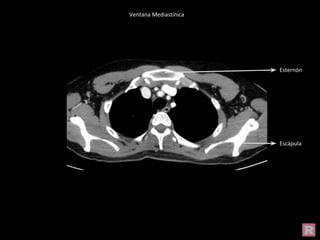

Ventana Mediastínica

Esternón

Escápula